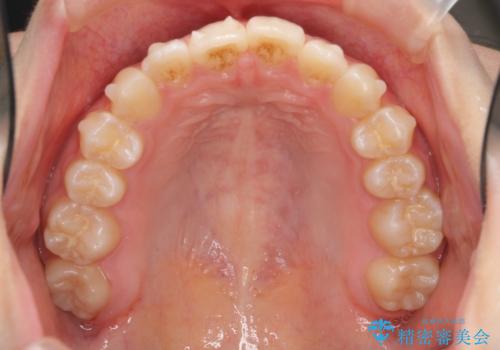

インビザラインライトで行う短期マウスピース矯正治療

- 前歯のガタつきを並べたいたいと、矯正治療を希望され来院されました。

とにかく短期間で前歯だけの治療を行いという希望が強く、全体矯正と前歯だけの部分矯正の仕上がりのイメージを確認したのち14枚のマウスピースで前歯のみの矯正治療を行っていくこととしました。

インビザラインライトは軽度なガタつきや傾斜の改善に用いられる全14枚のマウスピース矯正です。